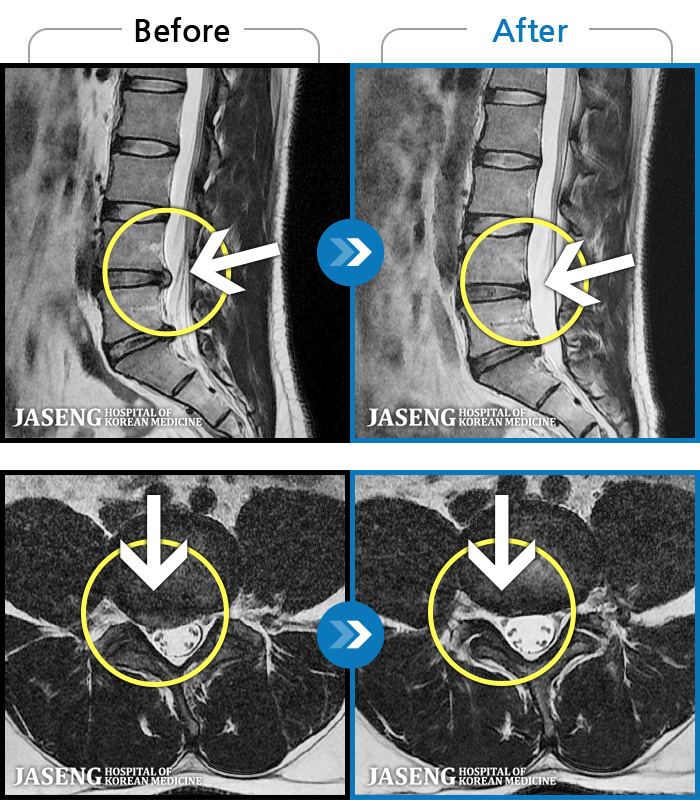

1,245 MRI ũ ʸ Ȯϼ.